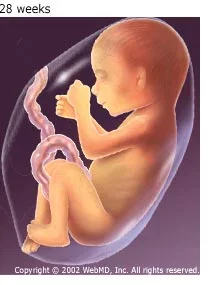

• weeks 28-29

weeks 28-29

Development of baby weeks 28-29

• Period: to

The baby's eyes begin to partially open. The central nervous system directs breathing and body temperature and the lungs can breathe. The baby now kicks and stretches and is at 10 inches and 2 1/4 pounds.